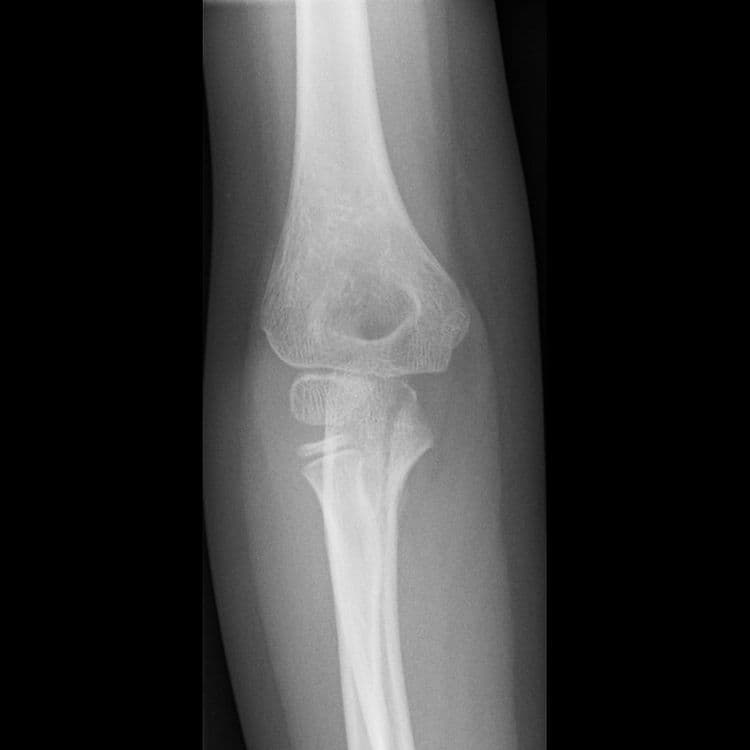

Comminuted Fracture - हाडांचा पूर्णतः चुरा होणे.